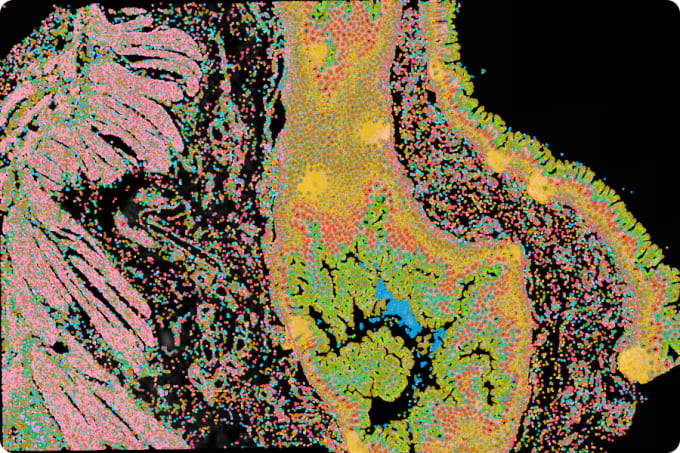

Xenium Mouse Brain Gene Expression Panel (2 rxns)

Xenium Human Breast Gene Expression Panel (2 rxns)

Xenium Human Brain Gene Expression Panel (2 rxns)

Xenium Human Lung Gene Expression Panel (2 rxns)

Xenium Human Multi-Tissue and Cancer Panel (2 rxns)

Xenium Mouse Multi-Tissue Atlassing Panel (2 rxns)

Xenium Human Colon Gene Expression Panel Kit (2 rxns)

Xenium Human Skin Gene Expression Panel Kit (2 rxns)

Xenium Human Immuno-Oncology Profiling Panel (2 rxns)